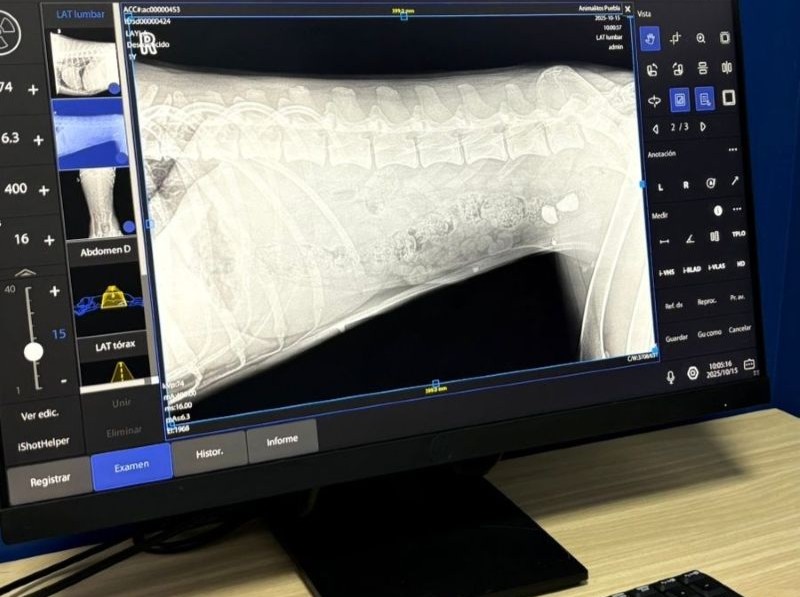

Rayos X

Tecnología e instalaciones de primer nivel

Equipo médico

único en México.